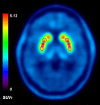

18F-FDOPA PET is one of the most widely used molecular imaging techniques to assess presynaptic dopaminergic activity. A variety of analytical methods have been developed to quantify 18F-FDOPA PET images and in most, the striatal-to-occipital ratio (SOR) is used as a quantitative parameter. A manual strategy is typically used for quantification purposes, which can have some caveats, being time-consuming and having some inter-rater variability. In the present study we aimed to test whether automated quantification methods can provide an efficient alternative to manual quantification to overcome its limitations and compare each method's capacity to discriminate between normal and abnormal subjects. 18F-FDOPA PET images of 60 subjects were analyzed and quantified with one manual and two automated methods. SUVRs were obtained for caudate and putamen nucleus in both cases. We were able to reach the same level of discrimination with manual and automated strategies, and a threshold for normal/abnormal discrimination could be obtained. We believe automated strategies for VOI quantification can help molecular imaging physicians in the process of interpretation of studies, making the process faster, yet reliable and objective.